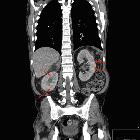

CT

- may show microcalcifications within the microcysts in the renal medulla and cortex